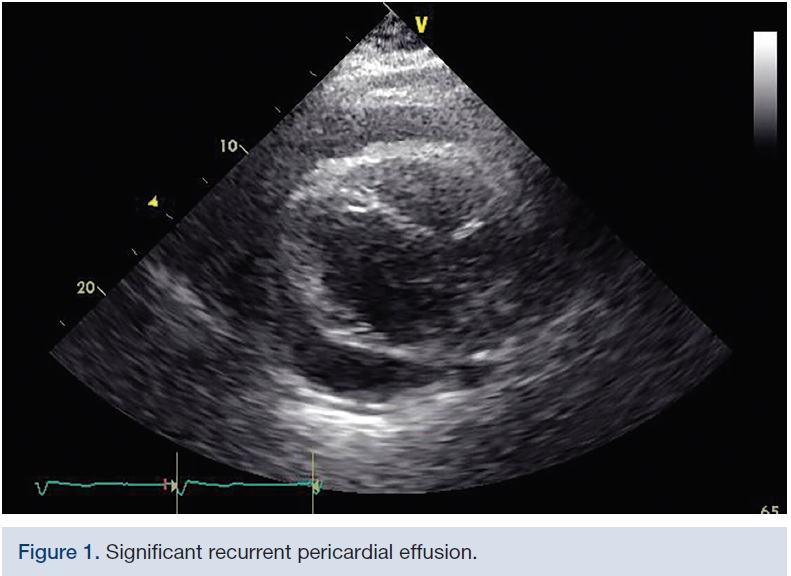

A 39-year-old female with past medical history of recurrent malignant pericardial effusions secondary to stage IV metastatic breast cancer, status post pericardial window placement two months prior, presented to hospital with complaints of worsening dyspnea. Transthoracic echocardiogram showed significant re-accumulation of pericardial fluid that was thought to be contributing to her symptoms (Figure 1). After pericardiocentesis with 800 ml of blood-tinged pericardial fluid, she came back to hospital with similar complaints in two weeks and repeat echocardiogram demonstrated significant pericardial fluid re-accumulation with tamponade physiology, at which point, palliative percutaneous balloon pericardiotomy was performed.